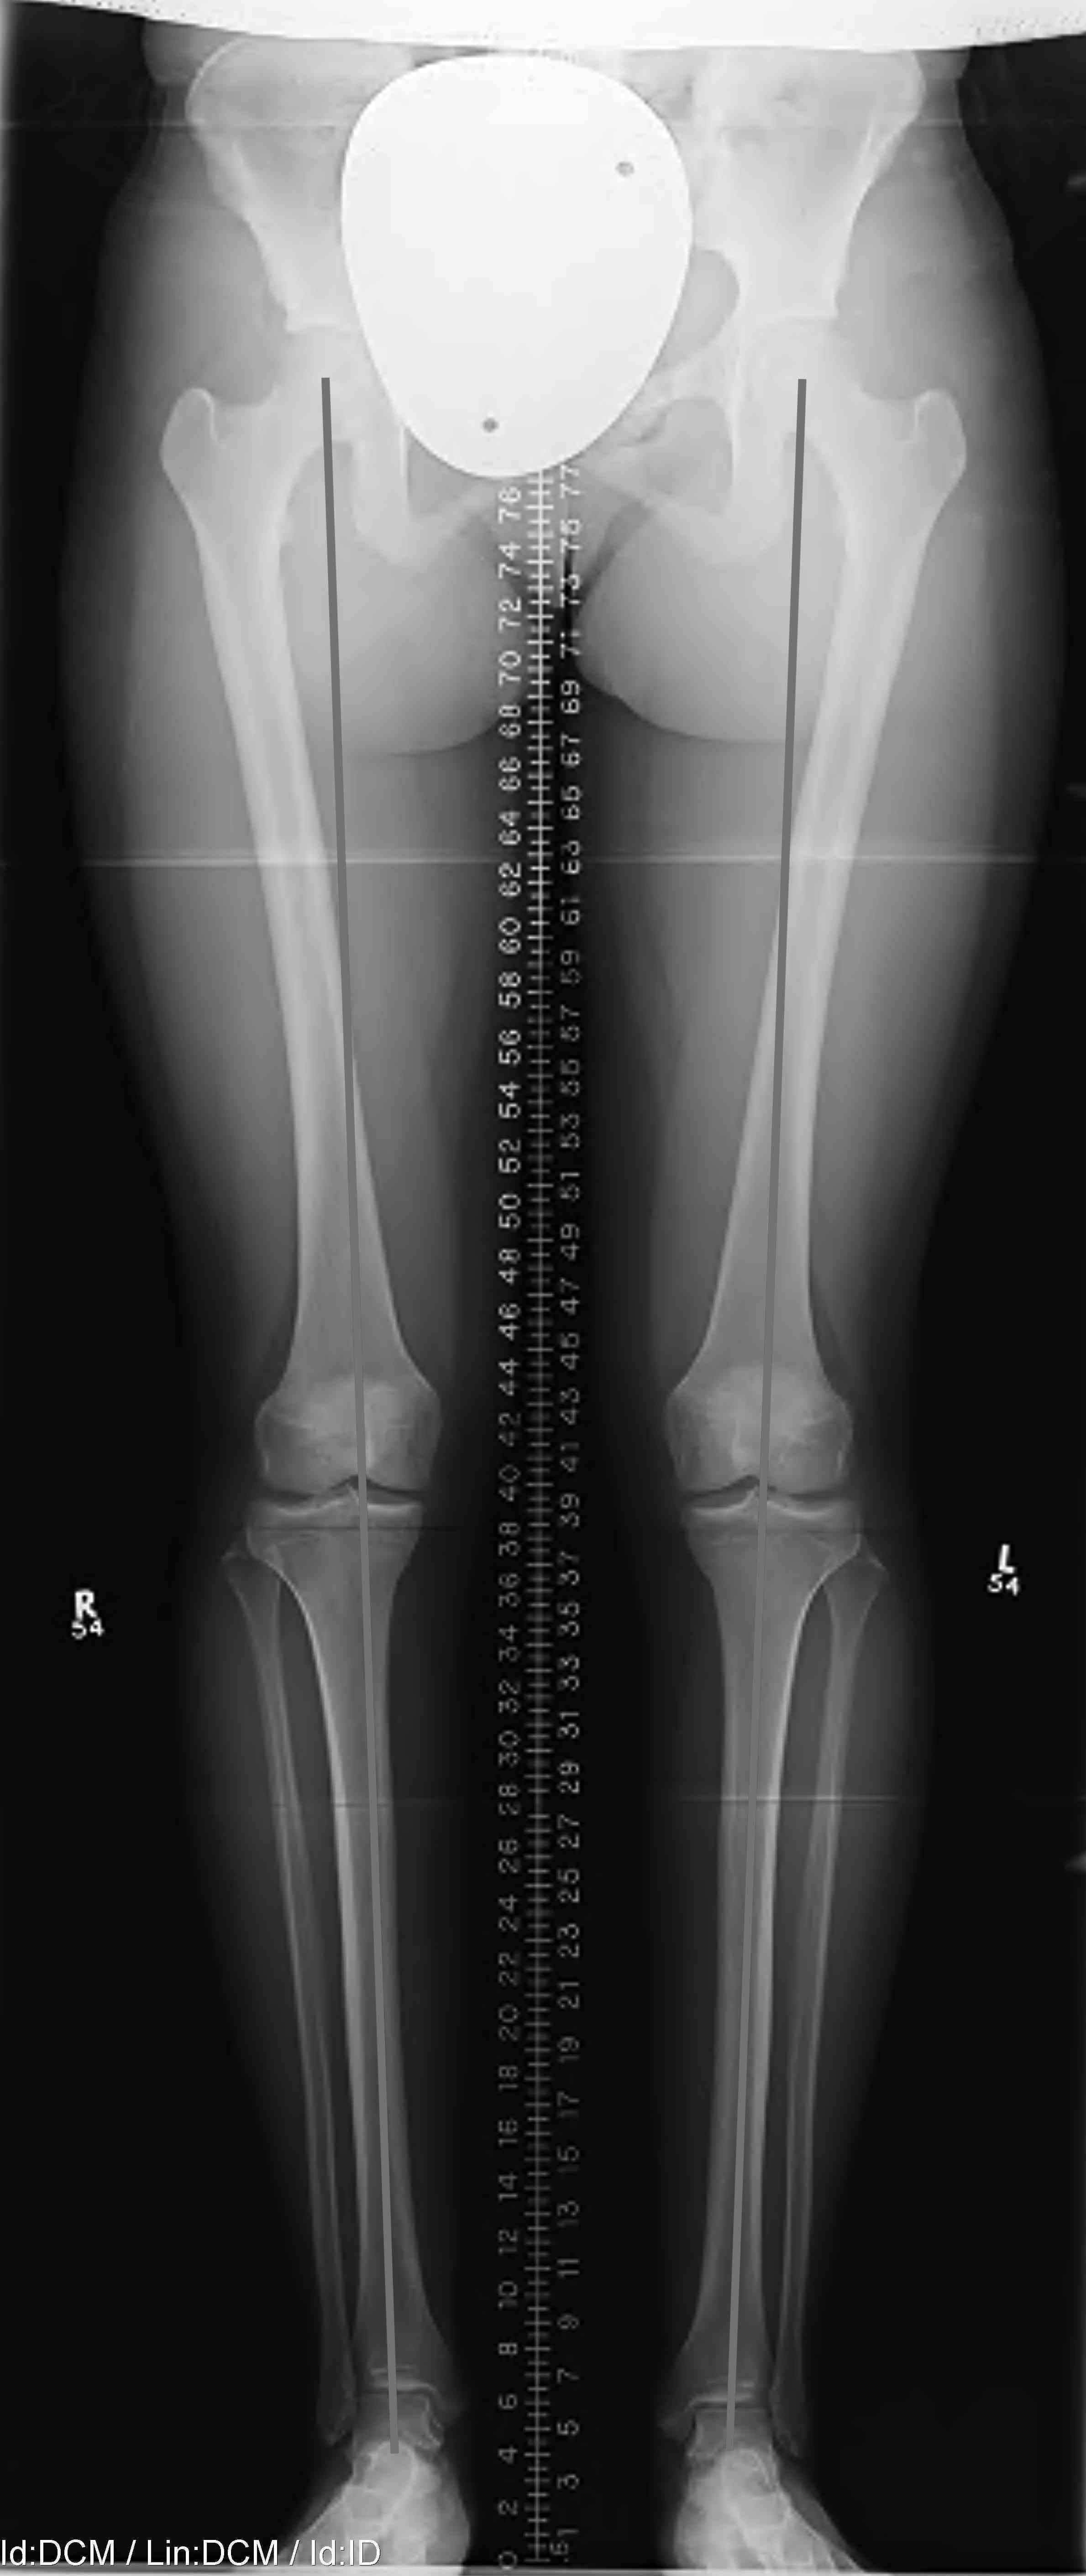

Long leg views

- assess for varus malalignment

Limb alignment

Mild varus of right knee

Definition Varus Malalignment

Mechanical axis passes medial to tip of medial tibial spine on long leg view